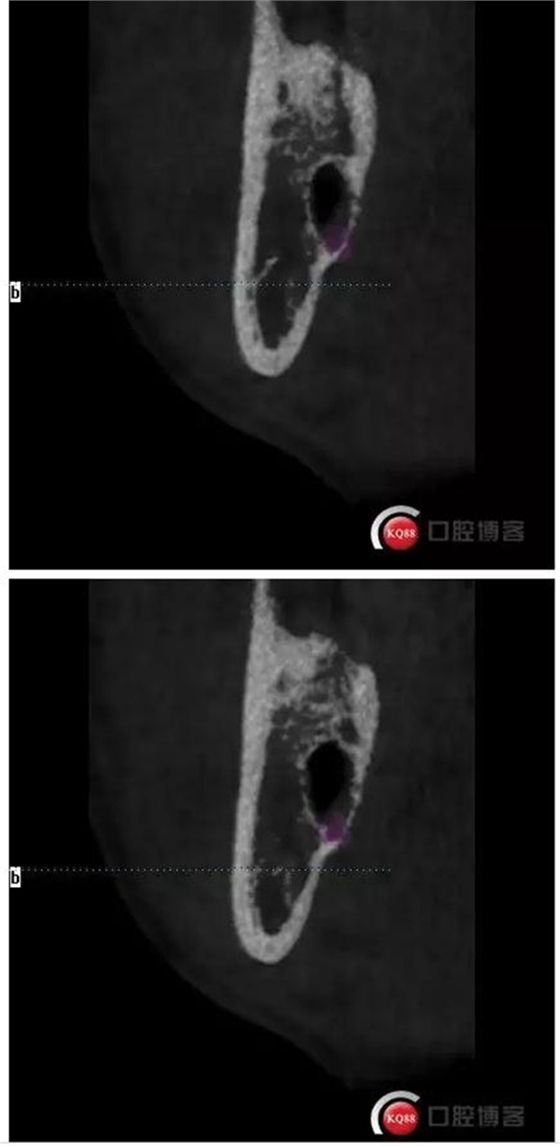

下面CBCT,可以看到兩個牙根的根尖三分之一在神經(jīng)管里面。

CBCT神經(jīng)管標(biāo)線,可以看到標(biāo)線不能連續(xù),中間被阻斷。